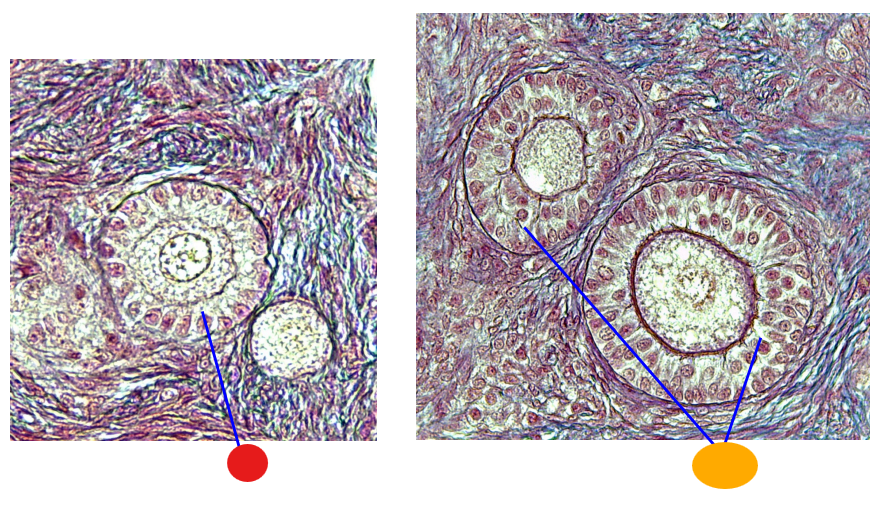

what is this

secondary follicle

what is this

tertiary follicle

what is this

tertiary follicle